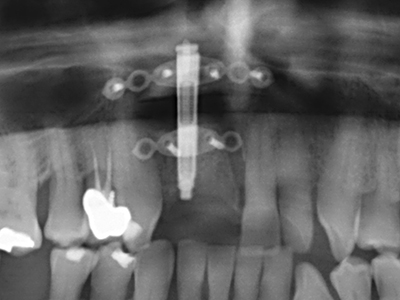

Indication: Sinus lift

Preparation of the lateral window during an external sinus floor elevation is challenging, particularly for implantologists with little surgical experience. Removal of the bone cover of the sinus without injuring the underlying Schneiderian membrane is only part of the operation – after establishing an adequate access, the membranous lining of the sinus must be carefully mobilized to make space for the augmentation materials or the implants. Piezo surgery is useful for this indication in two ways: diamond-coated instruments can be used for selective bone ablation and the underlying mucous membrane remains intact when the procedure is done carefully. The ultrasonic frequencies also enable detachment of the mucous membrane without complications – the frequencies are transmitted into the space between the mucous membrane and sinus floor by special blunt attachments (Cassetta, Ricci et al. 2012, Pereira, Gealh et al. 2014) (Rickert, Vissink et al. 2013). As a result, it is not surprising that current reviews of external sinus floor elevation positively evaluate the use of piezoelectric devices as well as the use of roughened implant surfaces and bone replacement materials (Wallace, Tarnow et al. 2012).